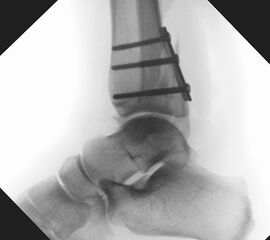

Die Versorgung von AO 44-B Frakturen erfolgt über einen längsverlaufenden lateralen Zugang. In der Regel gelingt eine suffiziente Stabilisierung mittels interfragmentärer Zugschraube (bei langem Frakturverlauf ggf. 2 Zugschrauben) und einer zusätzlichen Neutralisationsplatte (Abbildung 9 & 10).